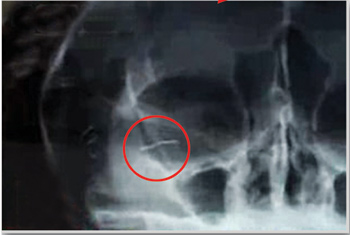

女子 金丝美容 遭毁容 皮肤溃烂脸上20多处包块(图) 医生诊断(图片来源:成都晚报) 华西都市报讯(记者